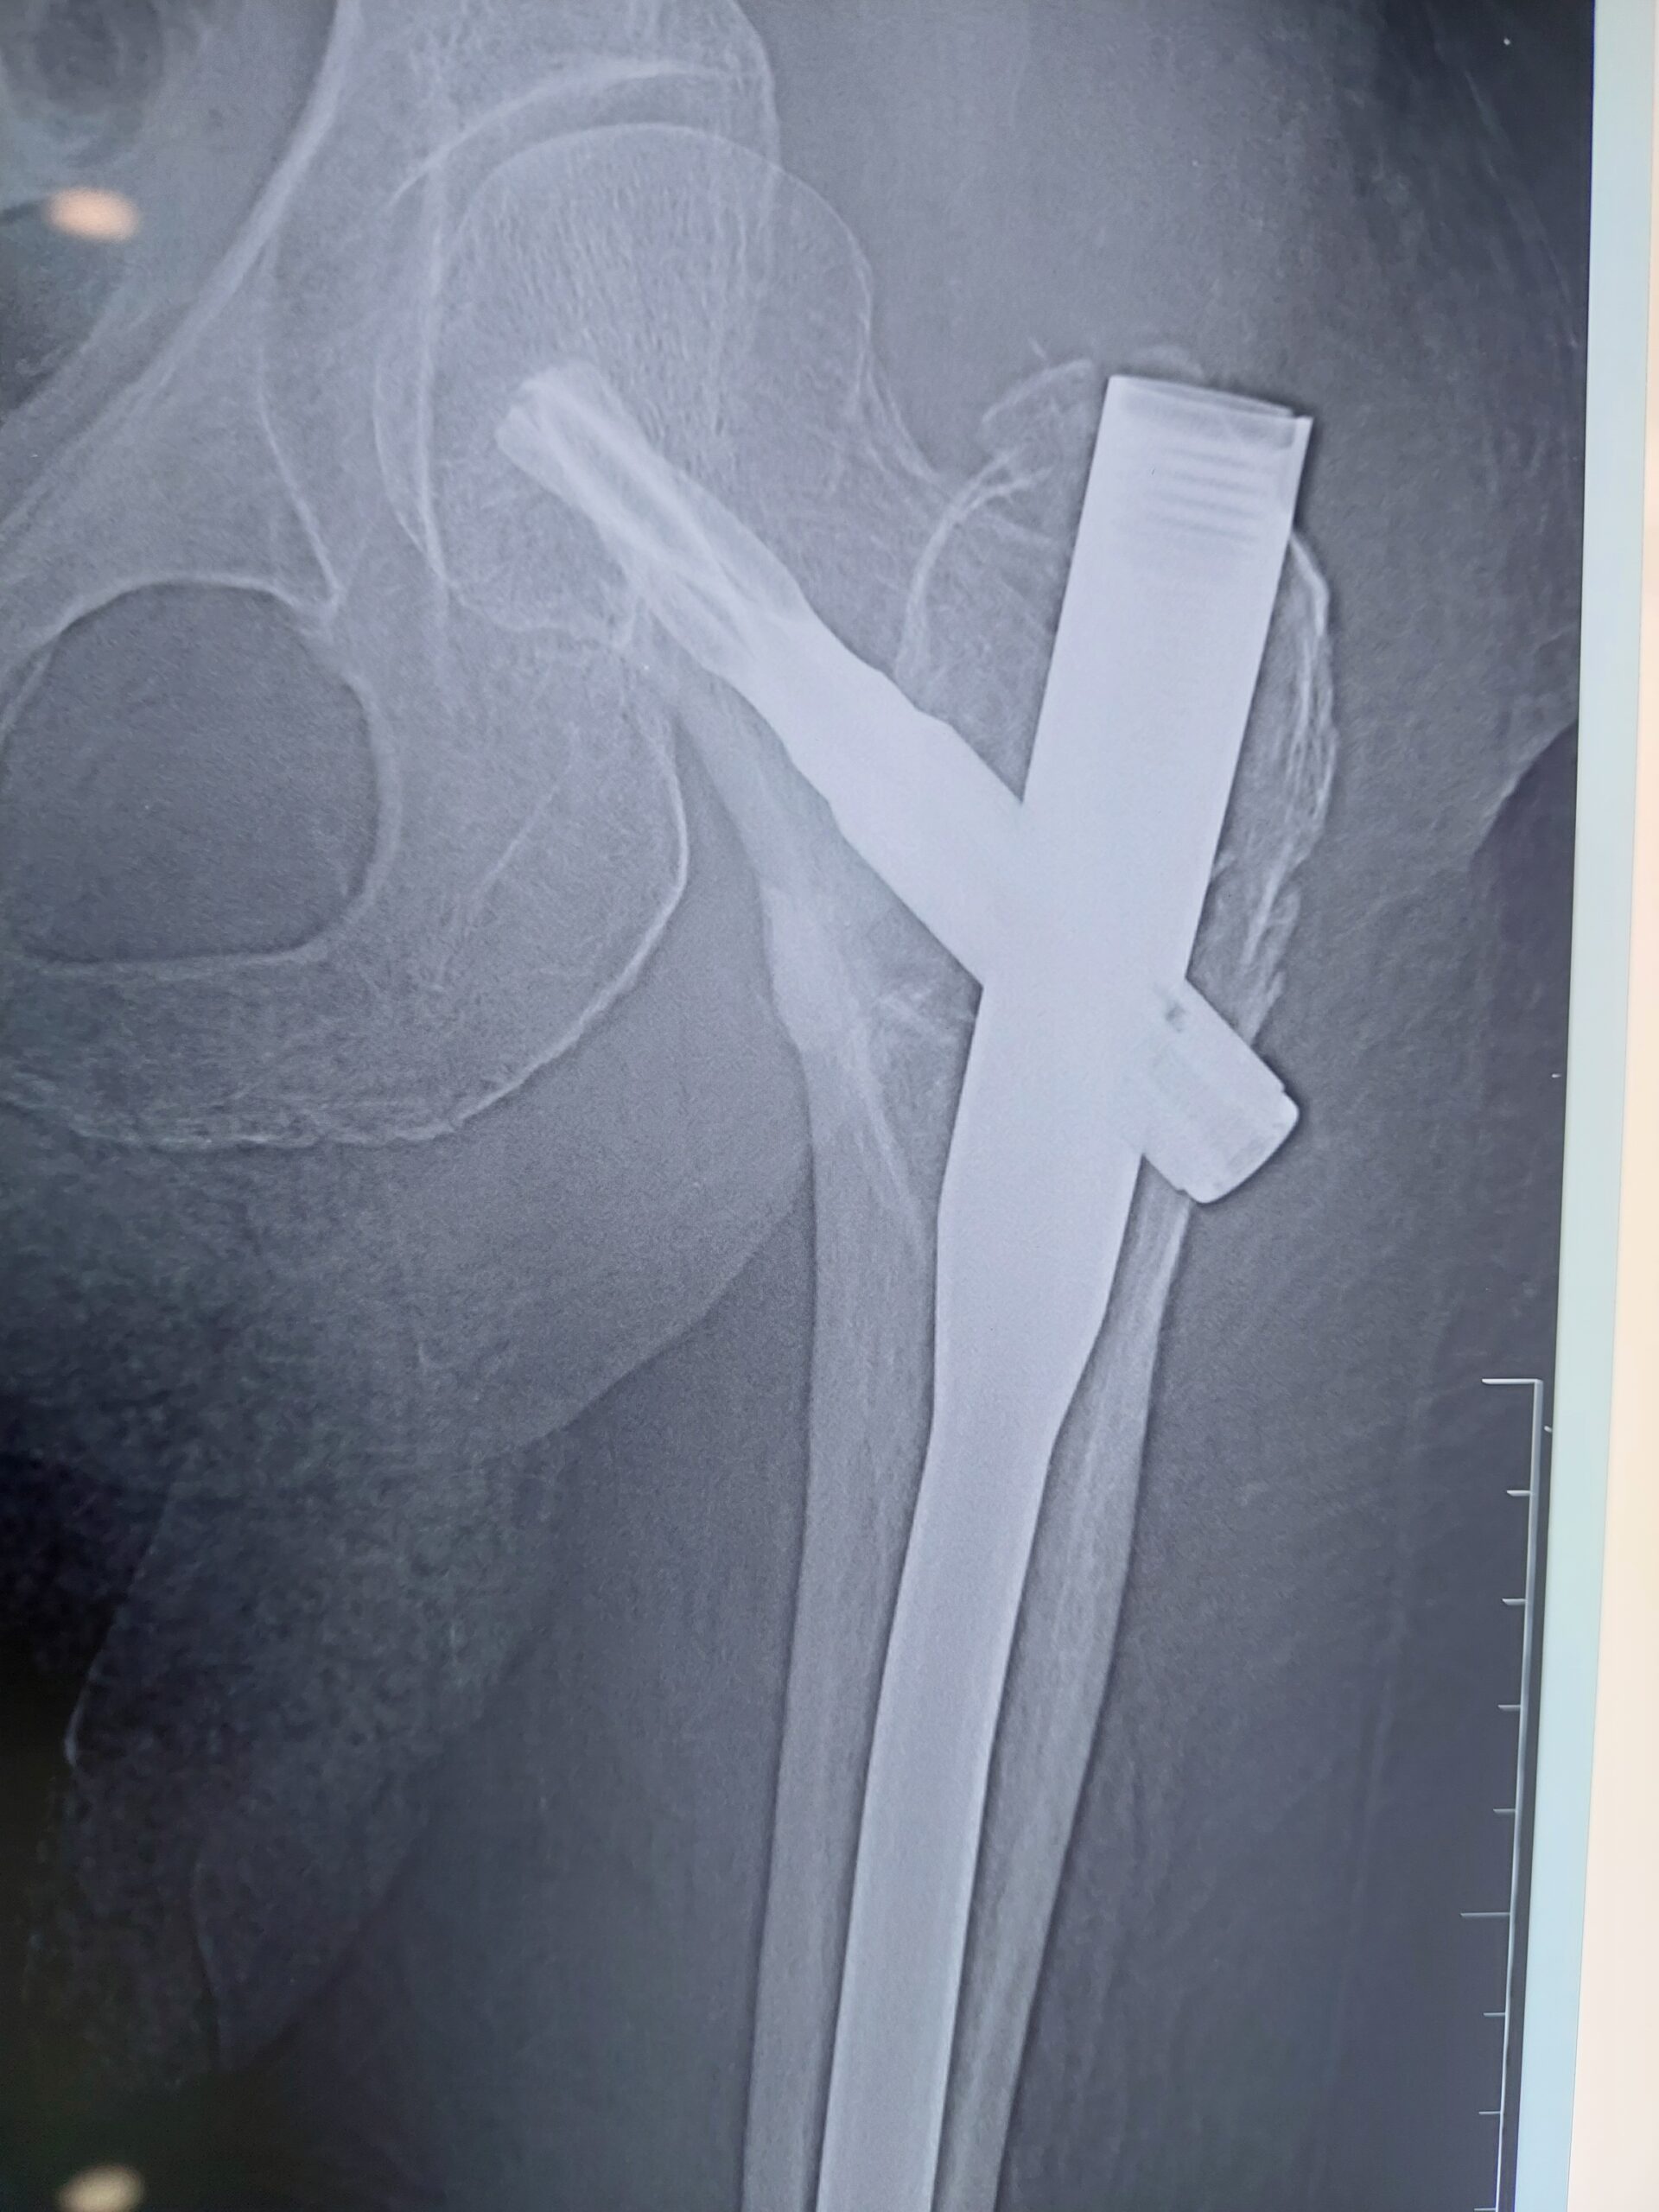

Bipolar Hip Replacement

The Orthopedic Surgeon replaces the femoral head using a two-part implant that allows better movement. Dr. Imran uses this procedure for patients with femoral neck fractures in hip joints. It is used for those who need better mobility without replacing the full joint.